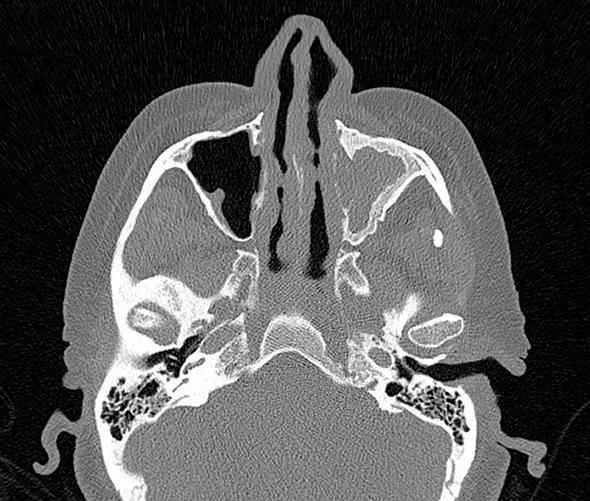

Nonsevere disease covers a wide spectrum of disease manifestations (Figure), which can have a substantial impact on patient quality of life. Management of nonsevere relapses has remained a challenge for which there has been an unmet therapeutic need.

Figure. Two aspects of nonsevere GPA as would have been eligible for treatment in the abatacept trial. (Top) CT demonstrating sinus mucosal disease. (Bottom) CT showing a lung nodule in a patient without respiratory compromise.